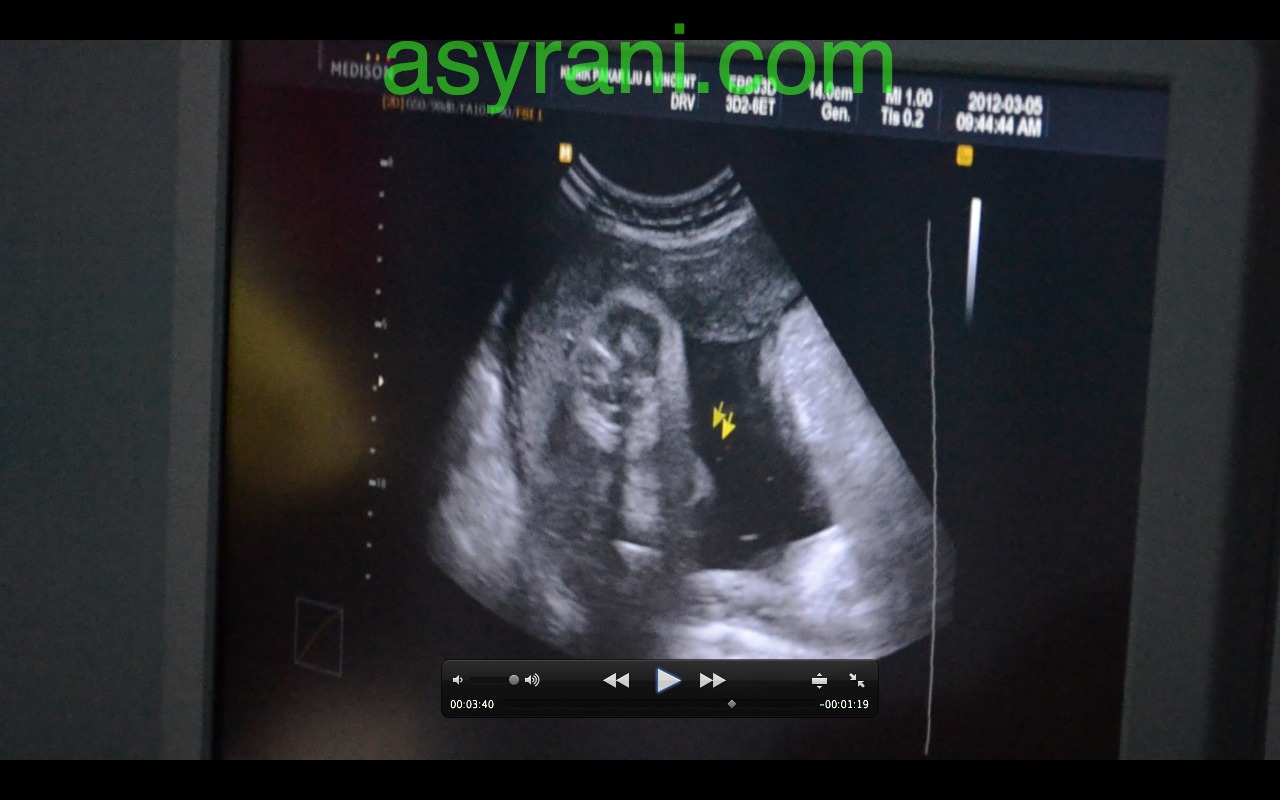

Pandangan sisi muka baby nampak hidung, diatasnya adalah uri (placenta)

Kaedah pengukuran untuk 3D (Proses untuk buat scan 3D)

Muka baby dalam bentuk 3D. Kelihatan hidung, mata dan bibir atas. Yang lain tertutup oleh uri dan bayang-bayang uri